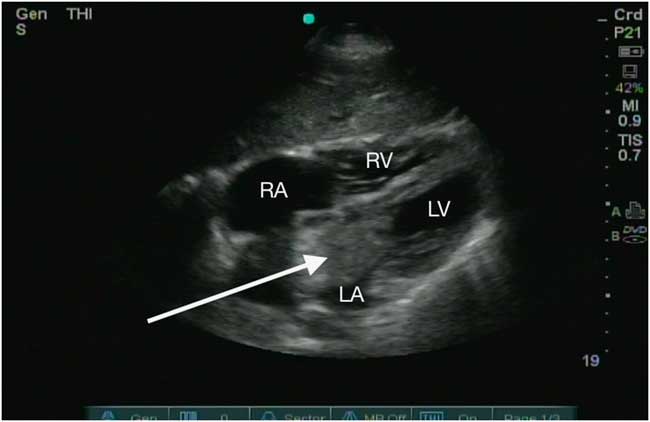

Figure 1 Apical four-chamber view of a left atrial myxoma (arrow) extruding into the left ventricle during atrial systole. LA=left atrium; LV=left ventricle; RA=right atrium; RV=right ventricle.

In the ED, her vital signs were within normal limits, and her physical exam was unremarkable. An electrocardiogram revealed normal sinus rhythm, and her troponin was negative. A point-of-care ultrasound demonstrated a 67-mm×35-mm hyperechoic lesion in the left atrium extruding into the left ventricle during atrial systole, resulting in moderate mitral regurgitation (Figures 1–3, Supplemental Videos 1–3). Both atria were dilated, and the left ventricular ejection fraction was normal. The mass was subsequently resected and diagnosed via histopathology as an atrial myxoma.